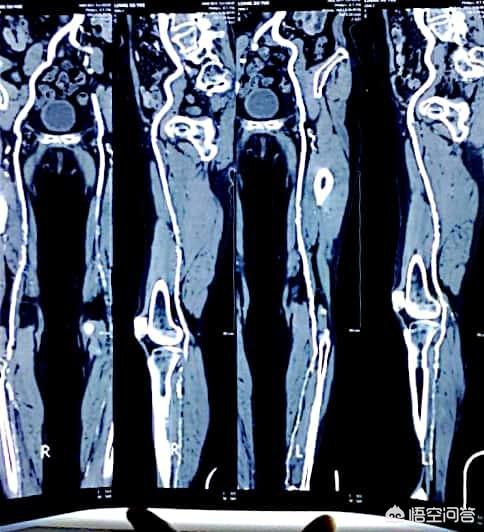

L'incidence du diabète est aujourd'hui vraiment très élevée, généralement chez les plus de cinquante ans, l'examen physique de dix personnes révèle au moins l'une des trois anomalies (taux élevé de graisse dans le sang, tension artérielle élevée, taux élevé de sucre dans le sang), et certaines présentent même les trois anomalies en même temps. L'apparition des trois hyperglycémies et le rythme de vie moderne ainsi que les habitudes alimentaires des gens sont étroitement liés, la figure suivante montre un patient diabétique présentant une plaque vasculaire au niveau des membres inférieurs :